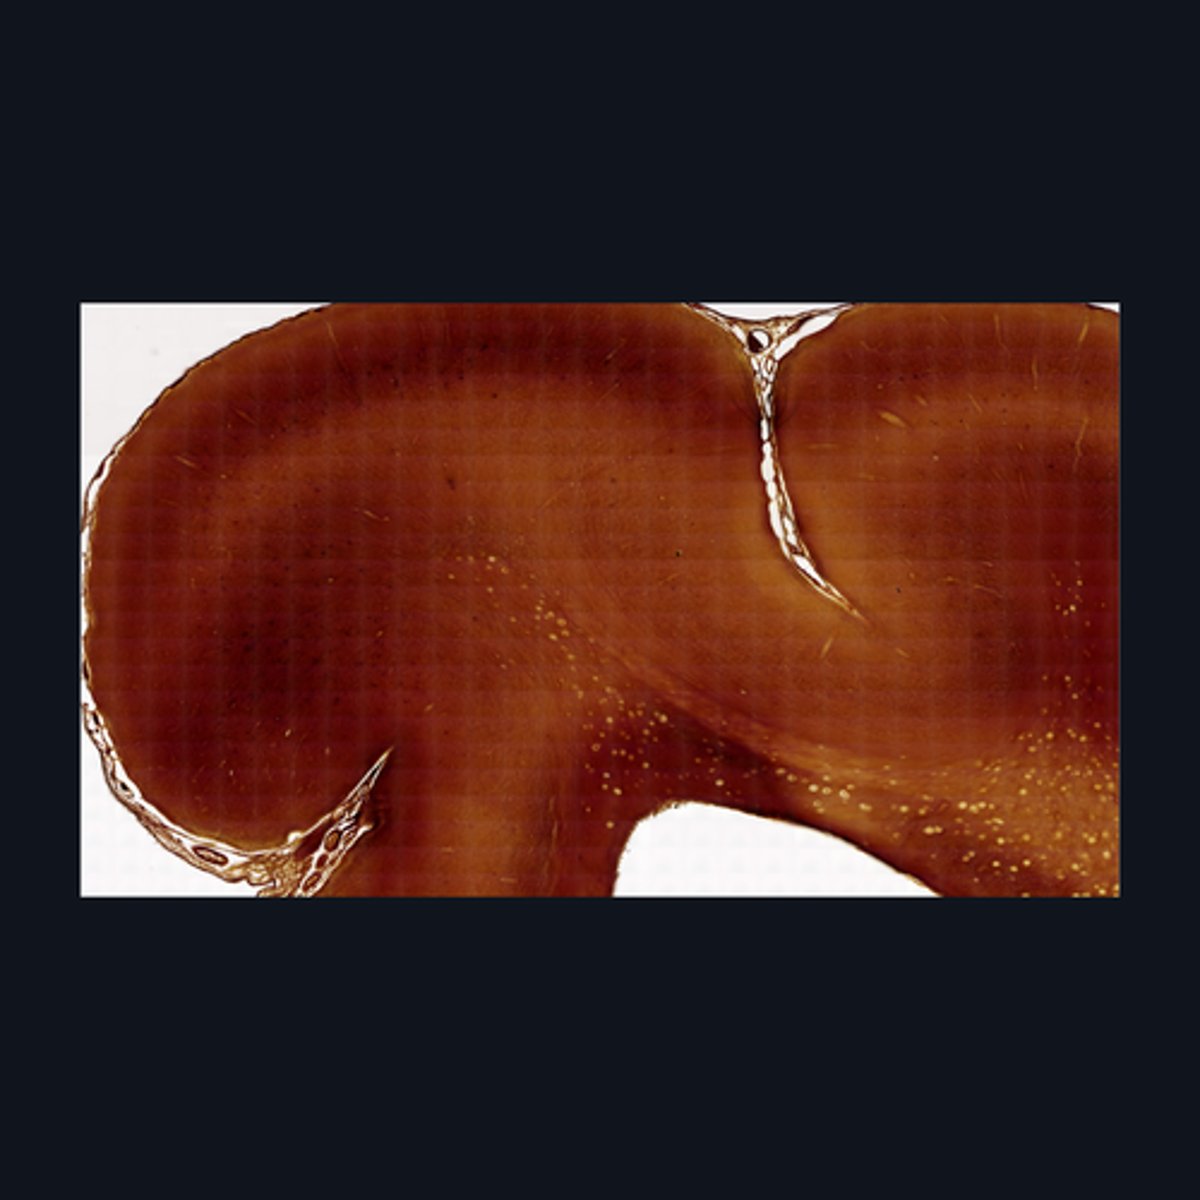

Gray Matter

Identify the pointed region in the spinal cord

(1) Ventral Horn, (2) Dorsal Horn

Identify the pointed regions of the gray matter of the spinal cord

Gray Matter (When looking at speciemen from the brain, all areas in the periphery are considered Gray Matter)

Identify the pointed region in the Cerebellum